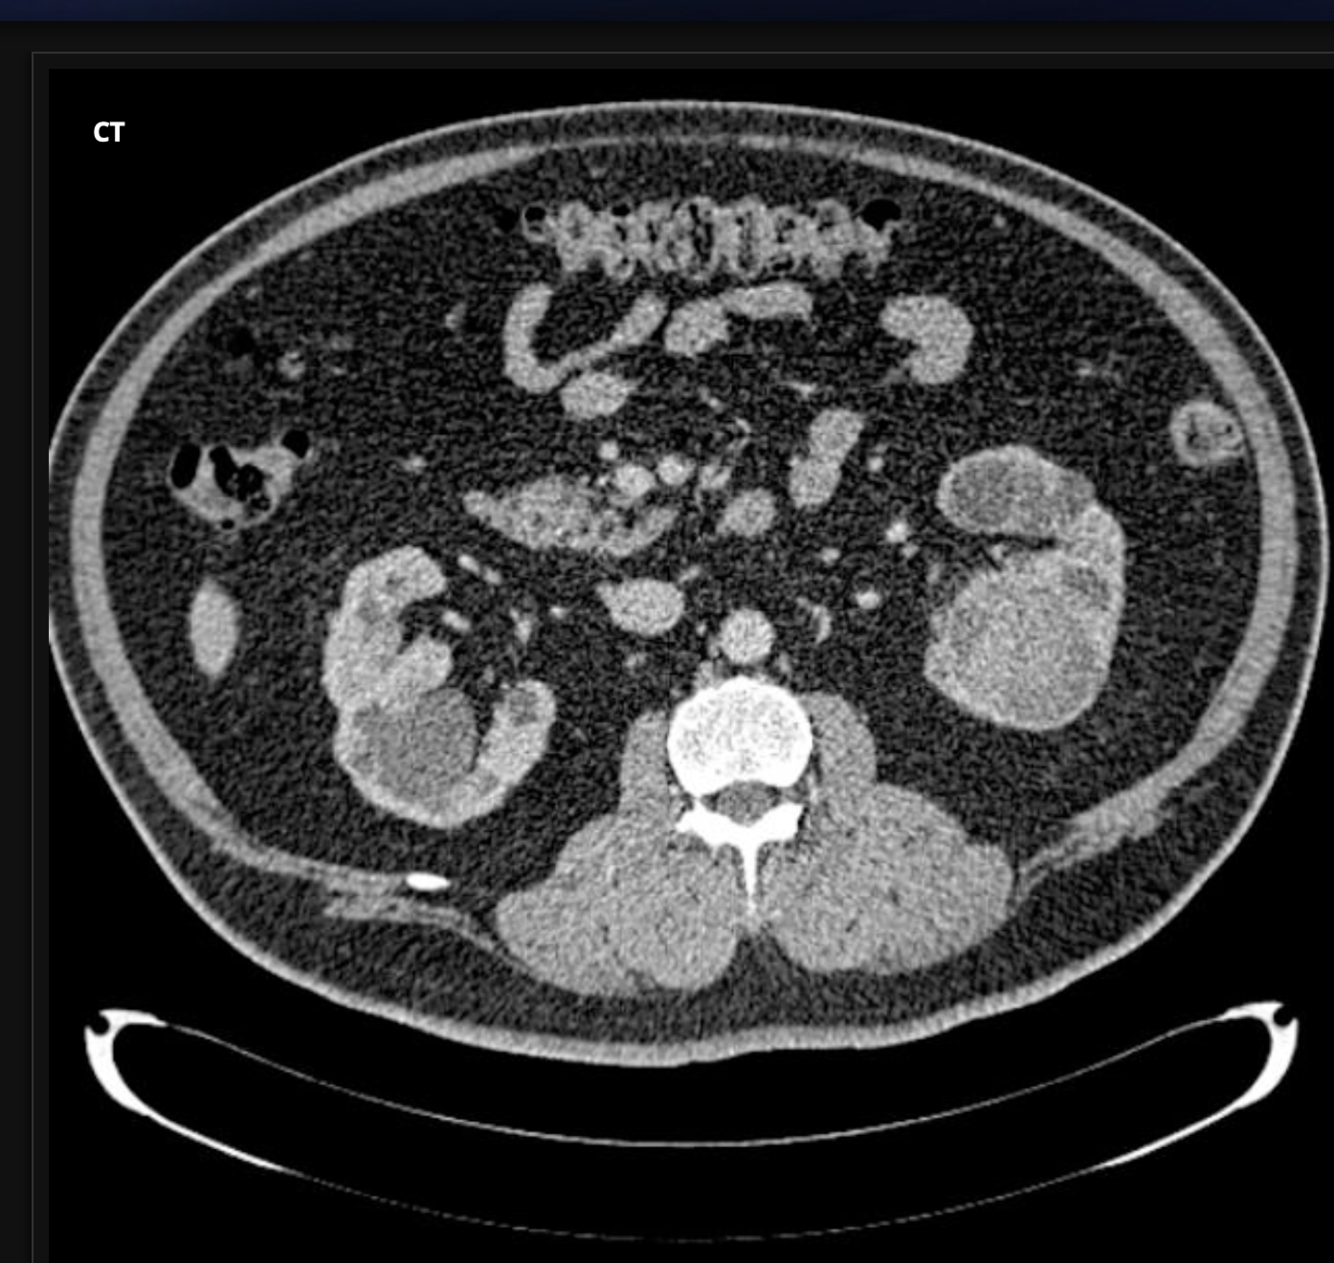

Case Discussion

what is this condition

who does it happen to?

Case courtesy of Dr Roberto Schubert, Radiopaedia.org, rID: 17489